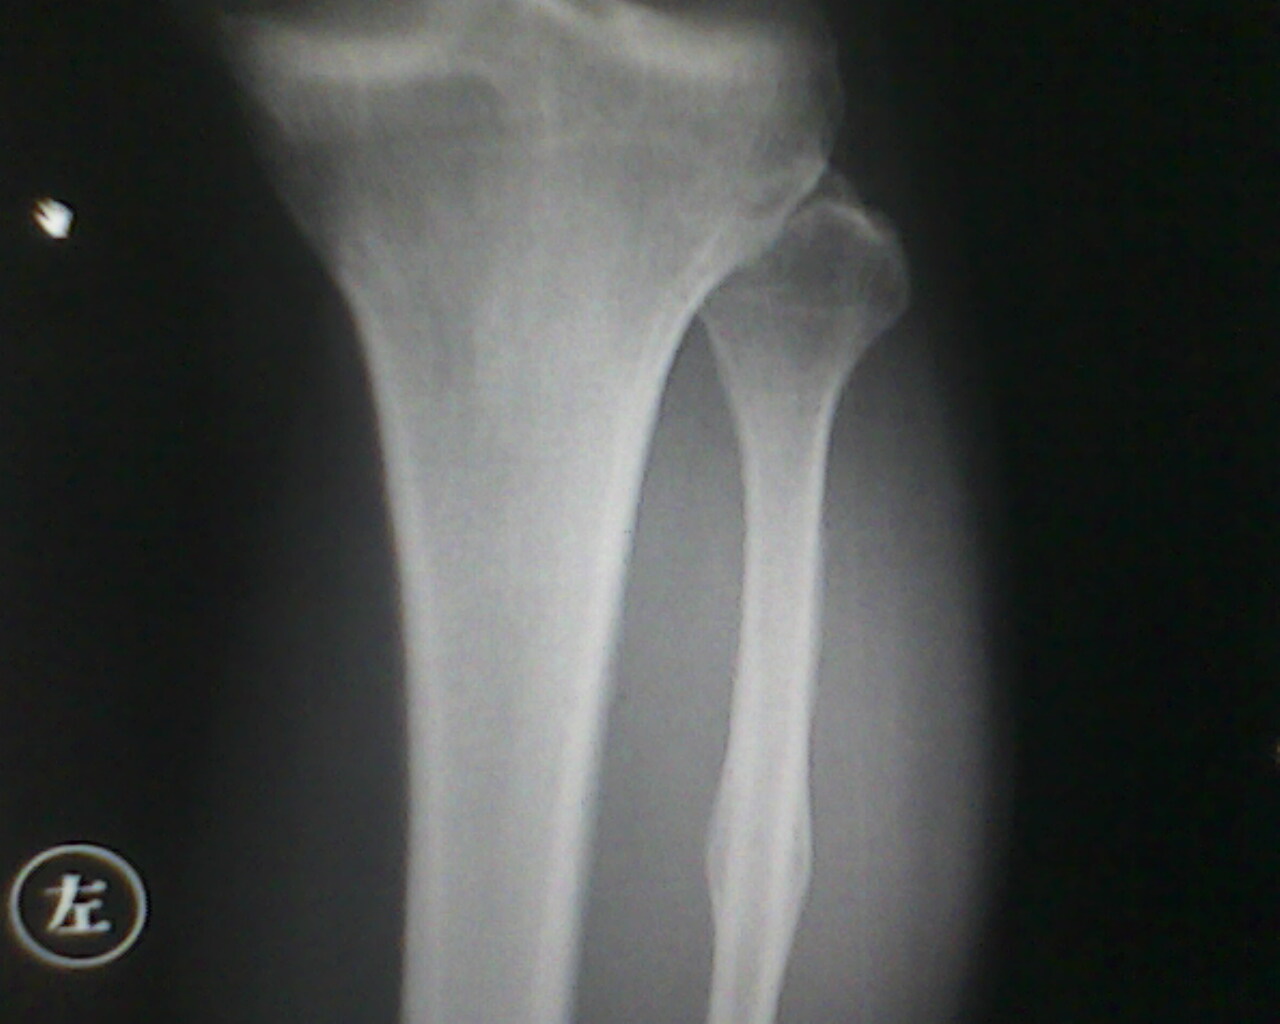

患者,男性  ,小腿肿胀。

不好意思。第二张翻了,大家讨论讨论腓骨病变

骨膜反应,软组织肿胀,未见骨质吸收破坏征象,当心骨肉瘤。建议ct检查

腓骨局限性梭形肿胀,支持首先往骨痂放向考虑,其他也不除外,随诊

首先可以肯定是个良性,疲劳性骨折(问病史,当兵的,长跑的,体育队的),陈旧性骨折(此前外伤没引起注意).

腓骨骨膜反应,骨质未见明显破坏,软组织肿胀。建议随访观察。